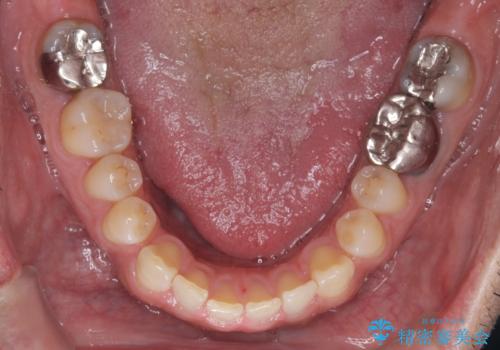

- お口の中にある銀歯を全てなくして、白く健康的な状態にしたい」という主訴でご来院されました。長年使用してきた複数の銀歯は、経年劣化により適合が悪くなっており、一部では内部で二次カリエス(虫歯の再発)も認められました。

患者様と相談の上、全ての金属(メタル)を取り除き、生体親和性が高く審美性に優れた素材へ置き換えるメタルフリー治療の計画を立案。部位や欠損の大きさに合わせ、セラミックインレーおよびセラミッククラウンを用いて、お口全体の調和を整えることとしました。

銀歯の除去と精密な再治療: 古い銀歯を一つひとつ丁寧に取り外し、内部の虫歯を徹底的に除去。神経を保護するための処置を行った上で、適合性を極限まで高めるために精密な型取りを行いました。

オールセラミックによる修復: 天然歯のような光の透過性と硬さを持つオールセラミックを使用しました。奥歯であっても、患者様固有の歯の色調や咬み合わせの溝を忠実に再現した修復物を装着。金属を一切使用しないことで、金属アレルギーのリスクを排除し、歯肉の色が黒ずむ心配もなくなりました。